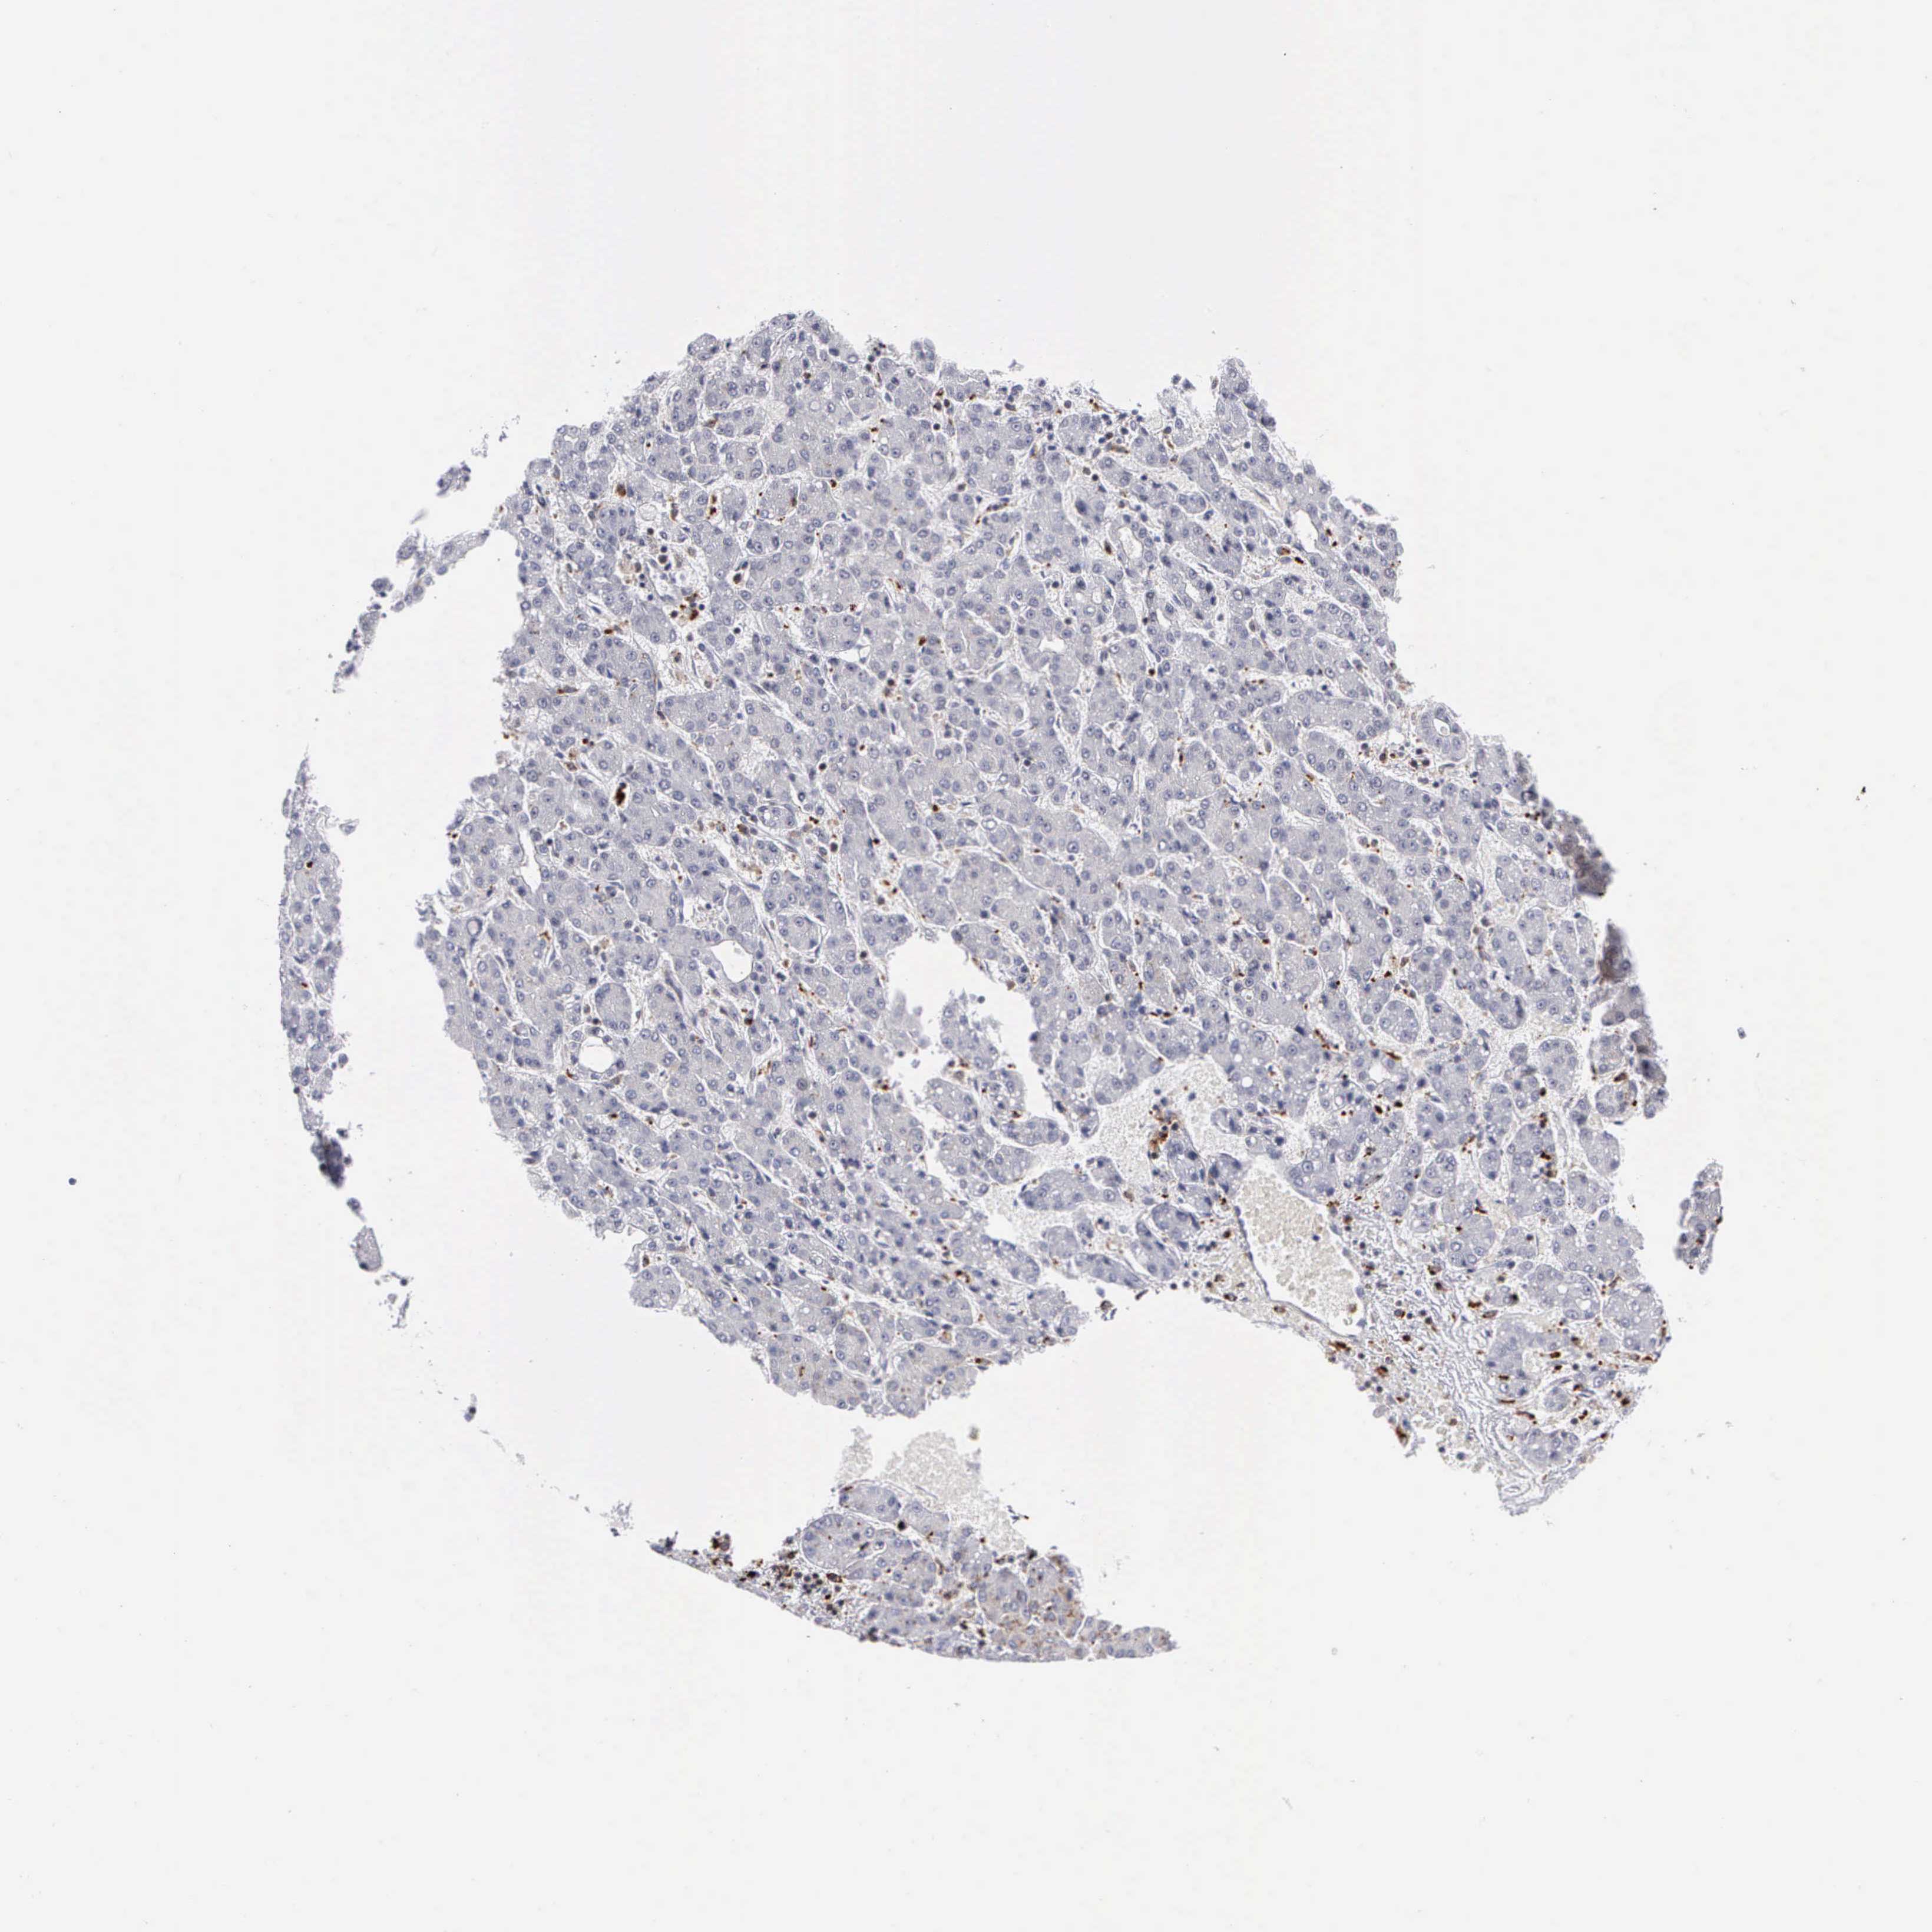

LIVER CANCER - Protein expressioni

A mouse-over function shows sample information and annotation data. Click on an image to view it in a full screen mode. Samples can be filtered based on level of antibody staining by selecting one or several of the following categories: high, medium, low and not detected. The assay and annotation is described here.

Note that samples used for immunohistochemistry by the Human Protein Atlas do not correspond to samples in the TCGA dataset.

Antibody stainingi

Antibody staining in the annotated cell types in the current human tissue is reported as not detected, low, medium, or high, based on conventional immunohistochemistry profiling in selected tissues. This score is based on the combination of the staining intensity and fraction of stained cells.

Each image is clickable and will lead to virtual microscopy that enables deeper exploration of all samples and also displays staining intensity scores, fraction scores and subcellular localization as well as patient and tissue information for each sample.

Antibody HPA003524

Antibody CAB000458

Staining

High

Medium

Low

Not detected

Intensity

Strong

Moderate

Weak

Negative

Quantity

>75%

75%-25%

<25%

None

Location

Nuclear

Cytoplasmic/membranous

Cytoplasmic/membranous,nuclear

Carcinoma, Hepatocellular, NOS

Cholangiocarcinoma